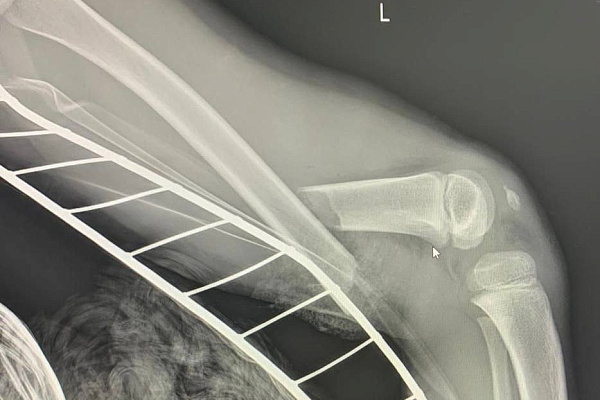

С открытым переломом, разрывом крупных сосудов и большой кровопотерей из поселка Фёдоровский в Сургутскую травматологическую больницу экстренно доставили 6-летнего мальчика. Тяжелую травму ноги он получил, катаясь во дворе на детской карусели.

Пациента принимал дежурный врач травматолог-ортопед Виктор Денисов (фото 3). По его решению в операционную срочно пригласили сосудистых хирургов из Сургутской окружной клинической больницы. Отломок бедренной кости пересёк бедренные вену и артерию. Длительное отсутствие кровоснабжения конечности могло привести к её потере. Нога уже была бледной и холодной. Но благодаря оперативной и высокопрофессиональной медицинской помощи необратимых последствий удалось избежать.

Ребёнка оперировали в течение двух часов. Пока специалисты СОКБ Дмитрий Лобанов и Дмитрий Ивченков (фото 4) сшивали сосуды и восстанавливали кровоток, Виктор Денисов возвращал повреждённую кость в правильное анатомическое положение и устанавливал аппарат внешней фиксации. С не менее сложной задачей в это время справлялись врач-анестезиолог-реаниматолог Александр Фицнер и медицинский брат – анестезист Вадим Держи – они должны были подобрать анестезиологическое пособие так, чтобы не усугубить состояние и без того тяжелого, потерявшего много крови пациента. Условия для одновременной работы трёх хирургов обеспечивала операционная медсестра Ольга Сорокина.

Сегодня ребёнок хорошими темпами восстанавливается в детском отделении травматологии и ортопедии под наблюдением Виктора Денисова, который в течение недели планирует выполнить еще одну операцию – окончательную коррекцию бедренной кости. О выписке из стационара говорить пока рано, но прогноз на перспективу благоприятный: опорная и двигательная функции ноги сохранятся в полном объёме.